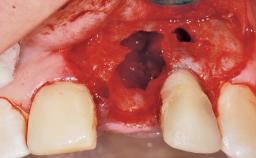

A 29-year-old female patient presented for treatment to replace the upper left central incisor tooth with an implant- supported restoration. The tooth had been intermittently symptomatic for the previous 12 months. The tooth had originally suffered trauma about 15 years previously. Several endodontic treatments had been performed, including an apicectomy procedure to retain the tooth. The patient was healthy and a non-smoker. She had reasonable expectations in regard to esthetic outcomes and the risk of marginal tissue recession following treatment. At medium smile, the gingival margins of the upper teeth were visible, with a display of 3 to 4 mm of the gingival margins. Gingival recession of tooth 21 and a discrepancy in the gingival levels between teeth 11 and 21 was observable during normal speech and smile.

Placement Protocol Immediate implant placement

Socket Integrity Damage to one or more bone walls

Bone Volume Damage to one or more socket walls

Esthetic Risk Medium

Risk of Complications High